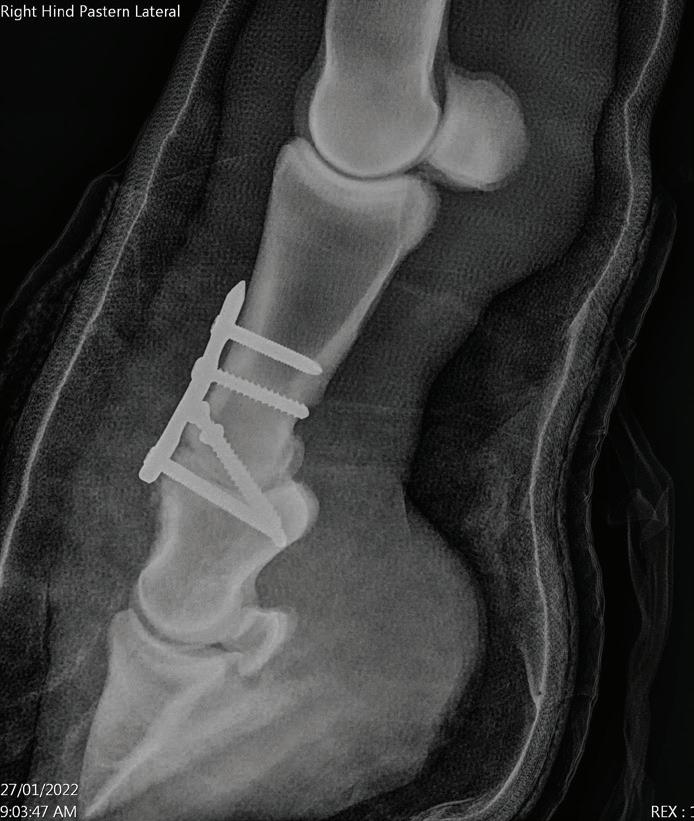

Case Report – Proximal interphalangeal (PIP) joint arthrodesis in a warmblood

32